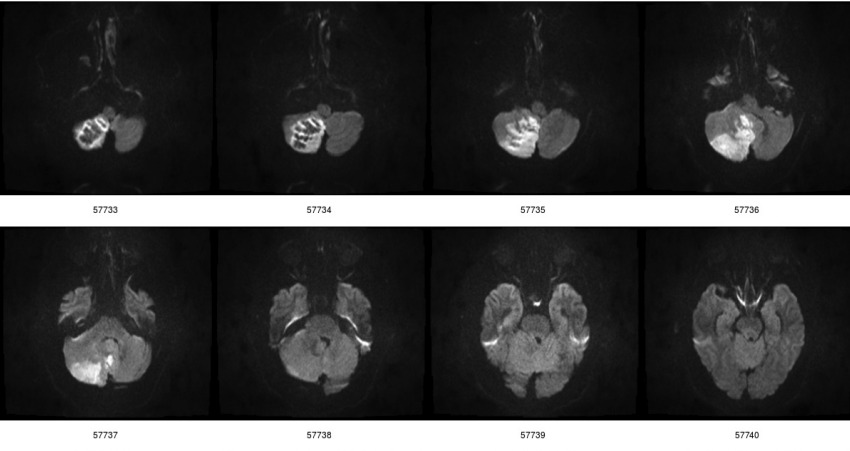

这是一个蒙太奇中有趣的部分

扩散加权图像。较浅的区域显示正常流体运动比大脑其他部分慢的区域。

这显示了该系列 30 张图像中的 8 张。这些被称为扩散加权图像,这意味着大脑中较浅的区域显示细胞内外的正常流体运动比大脑其他部分慢的区域。该扫描是在右侧小脑半球(在图像的左侧看到;这就是扫描图像的制作方式)中风的患者身上进行的。我的评估是,这些图像的质量与 CD 上的图像质量相同。